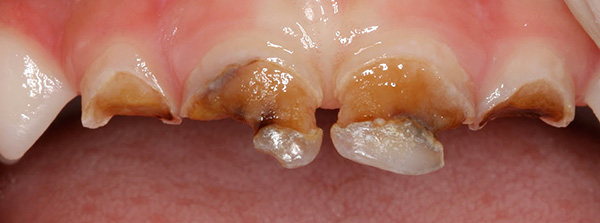

A foto mostra um exemplo de cárie no estágio de uma mancha branca nos dentes da frente de uma criança:

É essa etapa do processo carioso que pode ser revertida com um conjunto oportuno de procedimentos de recuperação - remineralização e fluorinação. Com o amolecimento adicional do esmalte, sua estrutura é destruída irreversivelmente, a cárie superficial é formada e, com o tempo, as bactérias começam a destruir a dentina.